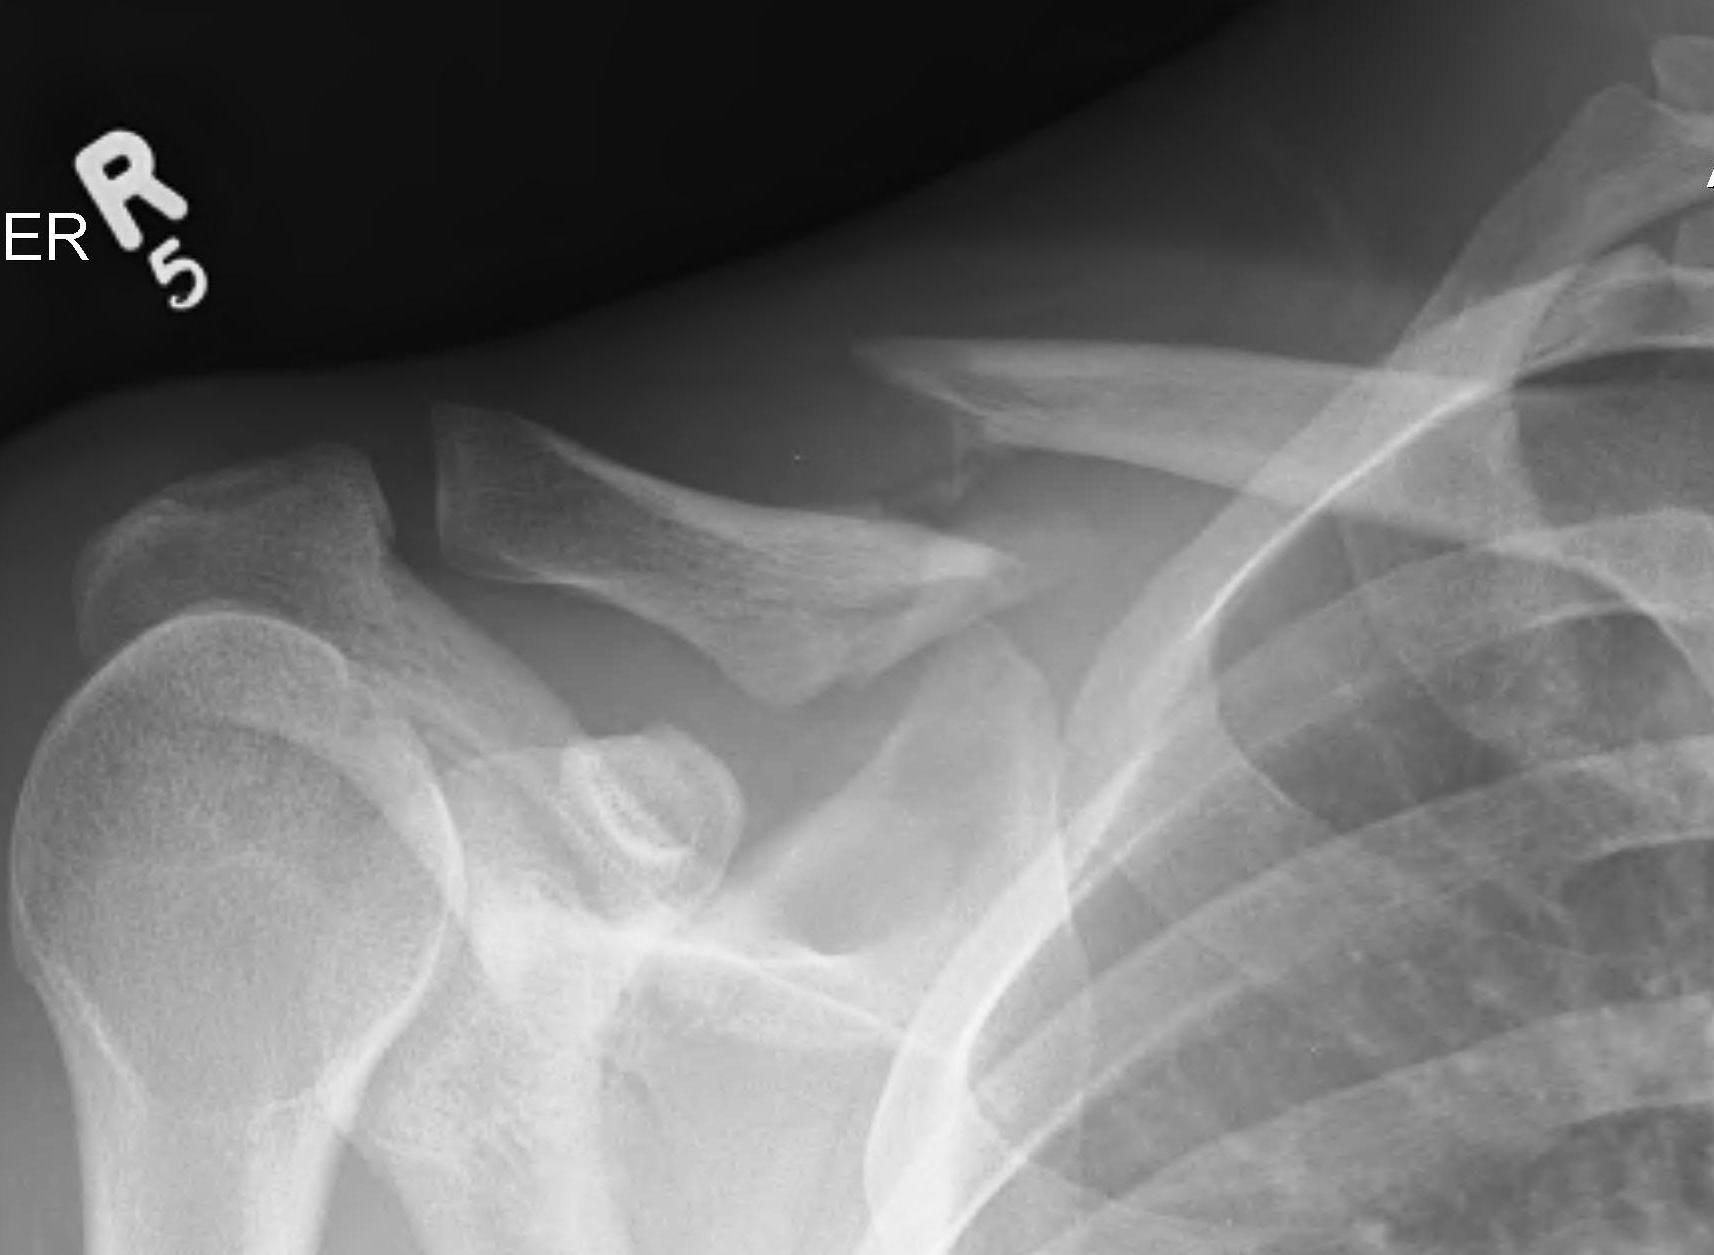

Compound clavicle fracture

Shorted / displaced midshaft clavicle fractures

Z shaped midshaft clavicle fracture